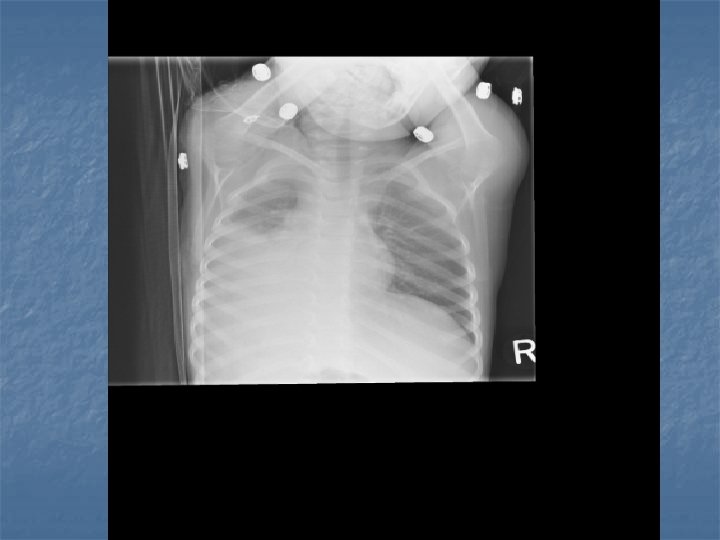

Pediatric CAP n n Bronchopneumonia – acute inflammation smaller bronchial tubes and peribronchiolar alveoli Pneumonitis Syndrome – Infants 1 – 3 months old, afebrile with cough, tachypnea and progressive respiratory distress. n n CXR shows diffuse pulmonary infiltrates and air trapping Single or mutlipathogens involved

CXR Findings VIRAL n Peribronchial thickening n Diffuse interstitial infiltrates n Hyperinflation BACTERIAL n Subsegmental, segmental or lobar infiltrates n Air bronchograms n Round pneumonia in early S. pneumo n n M. pneumo diffuse infiltrates out of proportion to clinical findings (or bronchopneumonia infiltrates in lower lobes) Bilateral reticulonodular interstitial infitrates

n n n 50% bacterial pneumonia will have lobar infiltrate Can also see alveolar infiltrates Round pneumonia seen with S. pneumo

When to admit pediatric CAP? n Toxic appearance Age <6 months Severe respiratory distress and O 2 requirements Dehydration/vomitting No response to oral abx Immunocompromised n Noncompliant patient/parent n n n